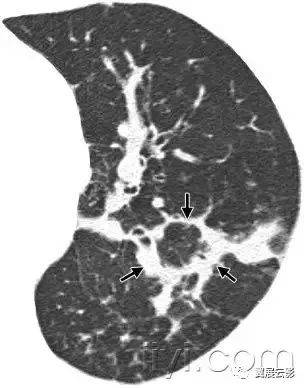

三十九、马赛克征

CT:本征象表现为不同的密度成片状镶嵌,可为间质性病变、闭塞性小气道病变(图)或者血管阻塞性疾病。马赛克征比马赛克样少血或者低灌注具有更强的诊断含义。由于支气管或细支气管阻塞导致的空气滞留可以导致局部的密度减低,在呼气相CT上表现更加明显。

该征象也可以见于间质性肺部疾病,特征是磨玻璃影,此时高密度代表间质性病变,低密度代表正常的肺。